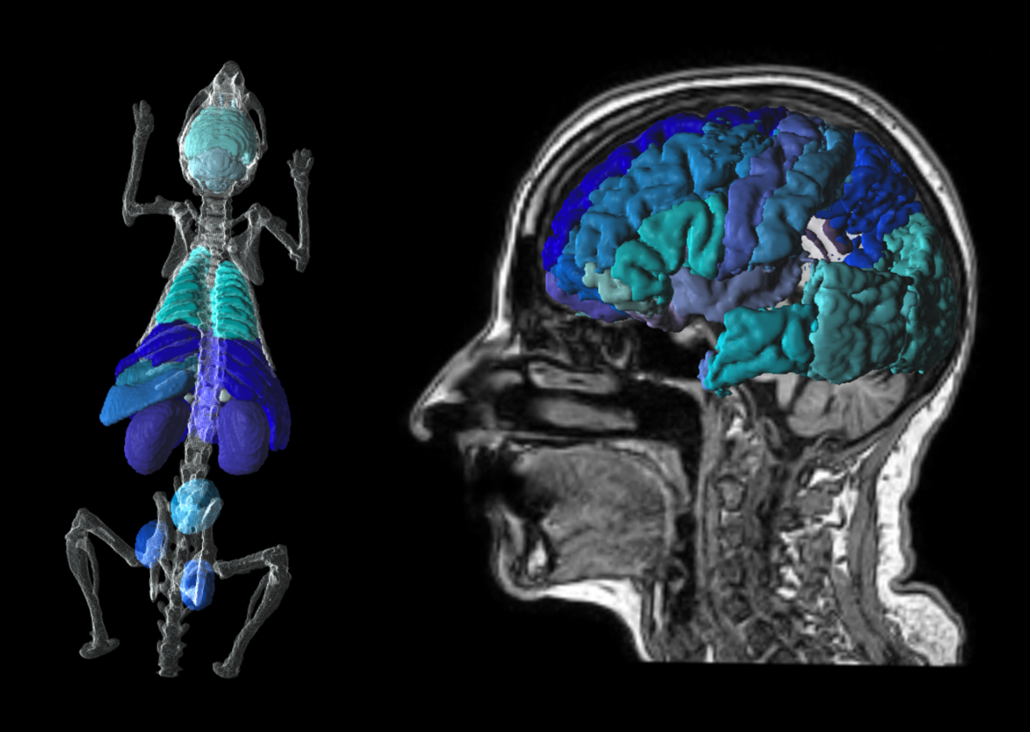

PNROD Rodent Brain Analysis

PNROD gives you brain segmentation workflows for small animal PET, PET/CT and PET/MR with the same direct access to statistics, kinetic modelling & parametric mapping.

P3D Extended 3D Rendering

Translational tools to go from mouse to man. Easily transform atlases from template to individual space. Create stunning visuals for publication.